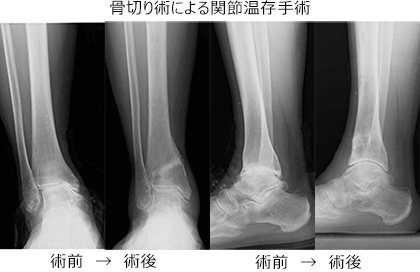

手術療法はそれぞれの部位・変形の程度に応じて、関節温存を目的とした骨切り手術、除痛・変形矯正のための関節固定術、人工関節置換術などが選択されます。

しかし、変形の強い変形性足関節症では、長期にわたり、痛みを確実に取り除くために、手術療法が必要となります。手術療法は関節固定術や関節温存手術、人工関節などがあります。我々は、リング型創外固定を使用した骨切り術による関節温存手術を積極的に行っています。末期の変形性関節症の方に対して関節固定術においても、関節鏡を用いた方法を行うことで侵襲を小さくする方法を行っています。また患者さんの状態に応じて、人工関節手術も行っています。